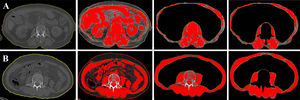

Determinaciones de la sarcopeniaPara calcular las mediciones de la sarcopenia se empleó el componente TC de la exploración PET/TC. El paquete informático de imagen (ImageJ, versión 2.0, National Institutes of Health, Bethesda, Maryland, EE.UU.) calculó el área total de músculo esquelético (AME, en cm2) a nivel de la tercera vértebra lumbar (L3). Se utilizaron las unidades Hounsfield para identificar la masa esquelética, con un rango umbral de −29 a 150 unidades Hounsfield. A continuación se calculó el IME normalizando el AME según la altura del paciente. Basándose en estudios previos, para determinar una sarcopenia se aceptaron como valores de corte del IME 44,77cm2/m2 para los hombres y 32,50cm2/m2 para las mujeres12. Se calculó el IMC como masa/altura2. Los pacientes se dividieron en dos grupos: aquellos con un IMC elevado (≥25) vs. aquellos con un IMC bajo (<25). En la figura 1 se muestran las determinaciones del IME de los pacientes con y sin sarcopenia.